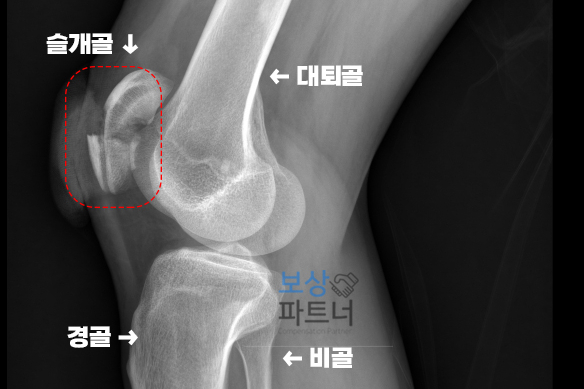

실제 의뢰인의 X-ray 영상 입니다. 빨간 박스로 표시한 부분이 바로 슬개골인데요. 뼈가 여러조각으로 분쇄골절 되었고 심지어 뼈가 피부 밖으로 노출되는 개방성 골절이었습니다.